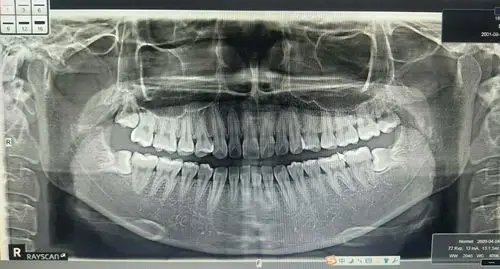

医学影像 #记录一下 一个七岁小朋友的口腔ct全景图,惊呆 - 抖音

2,拍摄口腔全景片,也就是口腔曲面断层片,覆盖范围广,一张全景片就能

2个版本的牙科全景x光片及前牙疼痛影像